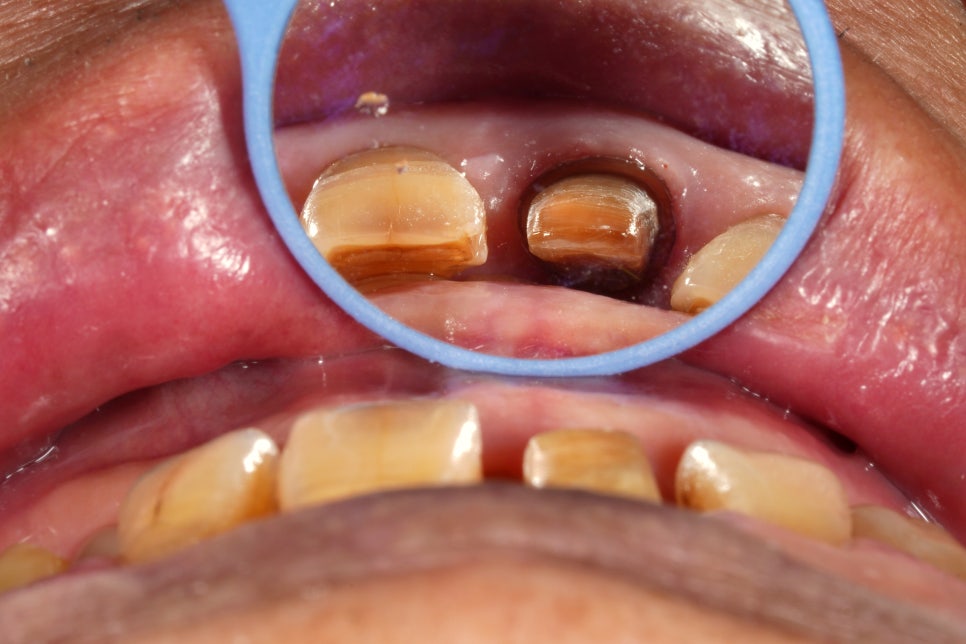

아무튼 치아를 다듬을 때는

깎은 치아의 장축이

인접한 대문니의 축에 대칭이 되도록 하면서

잇몸선도 대칭이 되도록 조절을 하고

일정한 두께의 마진(경계)를 주면서

치아 색상을 충분히 가려줄 수 있을 정도로

보철물 두께가 나오도록 했습니다.

경계부 두께가 일정하게 나오려면

치아를 둥글게 둥글게 깎는 게 아니라

역삼각형으로 깎는다고 생각을 하고

추후에 면과 면이 만나는 부분만 다듬어주는데요

다행히 생각한대로 됐다고 생각합니다.

씌운지 60년이 됐다고 한 치아는

왼쪽의 보철물인데요

저 보철물이 실제로 60년이 됐는지는 모르겠지만

(중간에 재치료를 받으셨을 수도 있고)

내면 접착제에서 세월이 느껴지기는 합니다.

처음부터 보철물 밑에 치아 뿌리가

훤히 들여다 보이게 치료하지는 않으셨을거예요

시간이 흐르면서

치아가 마모되고 움직이니까

처음 상태처럼 되셨을 거라고 생각합니다.